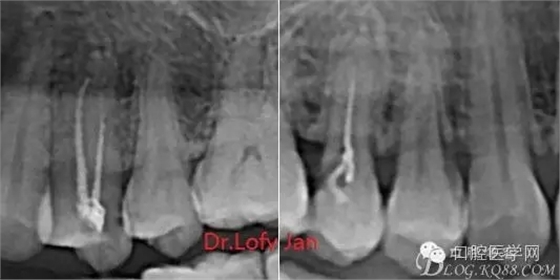

曲面斷層片在未試尖根管治療中的病例整理

前言:自己做的一些曲面斷層片在未試尖根管治療中的病例整理,發(fā)現(xiàn)問題很多包括自身的,技術(shù)的,還有設備的問題,予以總結(jié)整理并期待進一步提高。

病例分析:曲面斷層片在x線輔助診斷與檢查中目前大多數(shù)文獻和著作都建議只能作為初診拍片檢查手段,不能作為終末疾病的確診與手術(shù)療效的評價指標,臨床大部分中小型門診都因為設備不齊全導致信息偏差很大。